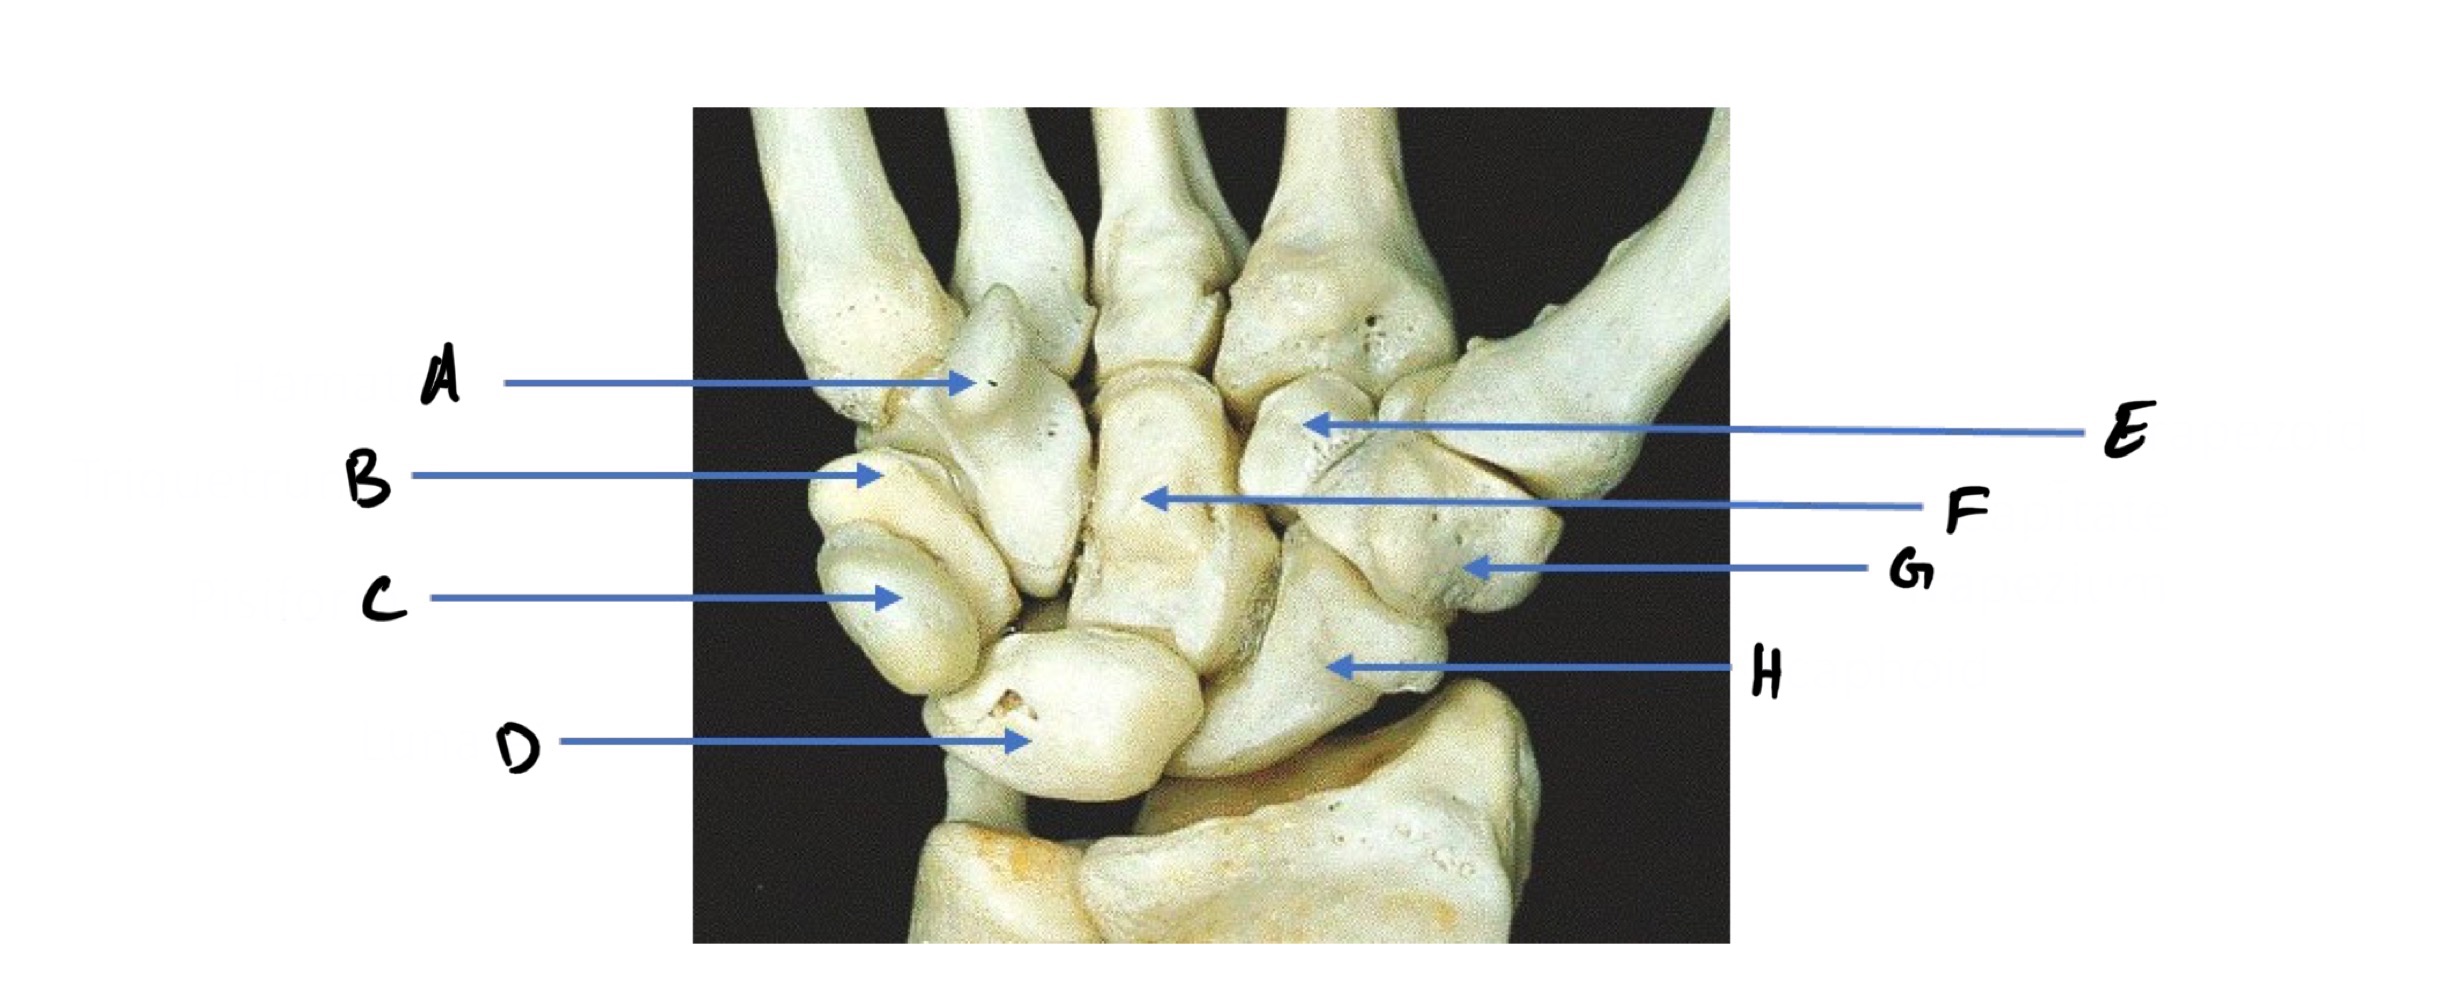

A

Hamate (Hammer shape)

B

Triquetrum

C

Pisiform (pea shape)

D

Lunate (like moon shape - lunar)

E

Trapezoid

F

Capitate (captain - biggest carpal bone)

G

Trapezium

H

Scaphoid